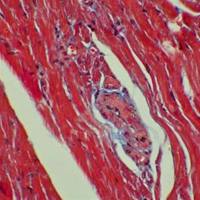

结果判读:钙盐沉积出呈深红色,背景淡红色或者近无色。

茜素红染色实验